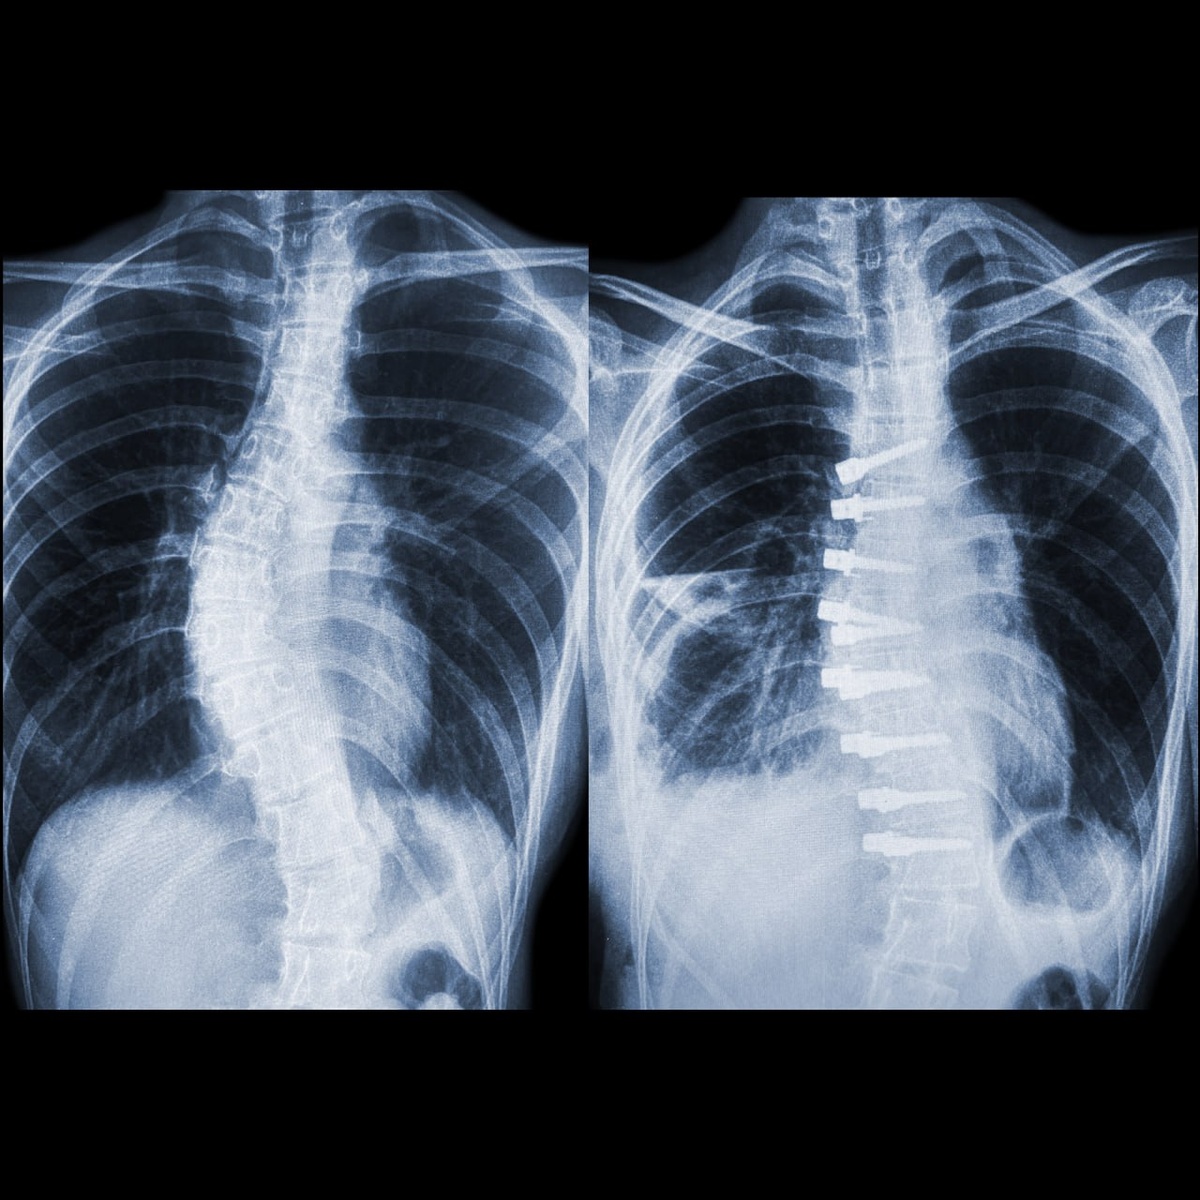

Одной пациентке еще нет 18 лет. Профессор отмечает отличный результат коррекции сколиоза в грудном отделе – «почти в ноль». Совершеннолетней девушке был полностью исправлен грудно-поясничный сколиоз IV степени.

«Вершина деформации расположена в области грудопоясничного перехода и сама деформация достаточно продолжительная. Особенность в том, что чаще всего при операциях с динамической системой достаточно короткая область фиксации, а в данном случае использованы 17 винтов на 10 позвонках с Т7 до L4», - рассказал Сергей Колесов.